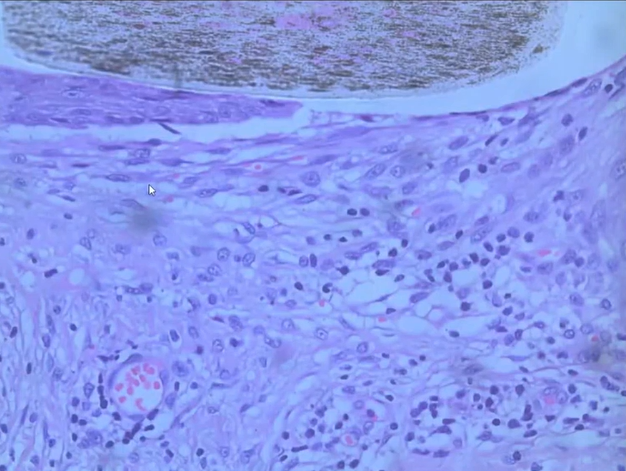

于是取了病变部位做病理检查,枕部表皮大致正常,双毛干、真皮毛囊周围大量浆细胞、淋巴细胞浸润,真皮浅中层纤维结缔组织增生伴血管扩张,血管周围较多淋巴细胞、浆细胞浸润。

临床诊断:束状毛;毛囊炎;瘢痕性脱发